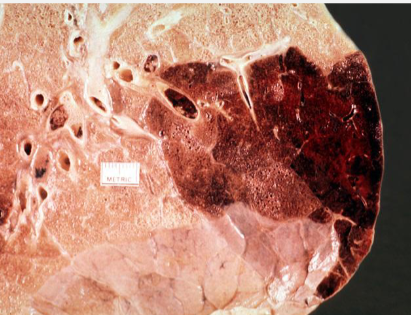

term image

Red Hemorrhagic Infarct

Pulmonary embolism